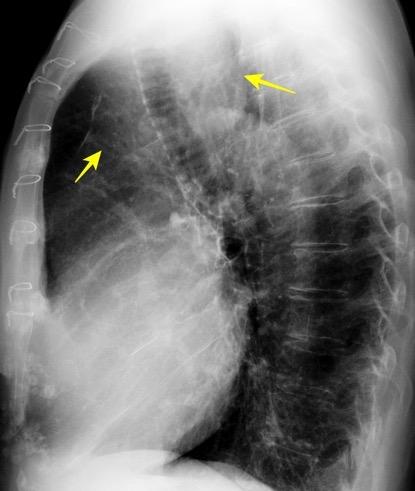

Triada de Garland

Ganglios paratraqueales derechos e hiliares bilaterales

95% de pacientes tienen ganglios hiliares bilaterales aislados o con afectación mediastínica (espec. paratraqueal derecho).

Criado E et al. Pulmonary sarcoidosis: typical and atypical manifestations at high-resolution CT with pathologic correlation. Radiographics. 2010